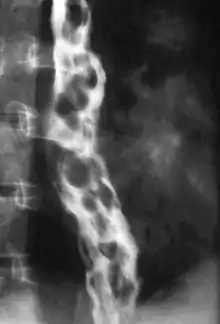

دوالي مريئية

الدوالي المريئية (بالإنجليزية: Esophageal varices) هي توسع في الأوعية الدموية الموجودة في الأغشية المبطنة لتجويف المريء، تظهر غالباً في الجزء السفلي من المريء وعادة ما تكون ناتجة من فرط ضغط الدم البابي. لفرط ضغط الدم البابي عدة أسباب إلا أن أكثرها شيوعاً هو التشمع الكبدي. يعتبر النزف الحاصل من الدوالي المريئية أحد أهم الاختلاطات الطبية المصاحبة للحالة وعادة ما يتم تشخيصه وعلاجه عبر التنظير الداخلي.[2]